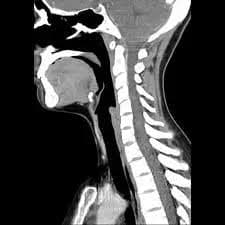

Discover the causes of your neck pain with a Cervical CT Scan! Fast and reliable results with expert radiologists. Click for MRI imaging and check-up packages!